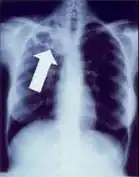

2. Any cavitary lesion - Lucency (darkened area) within the lung parenchyma, with or without irregular margins that might be surrounded by an area of airspace consolidation or infiltrates, or by nodular or fibrotic (reticular) densities, or both. The walls surrounding the lucent area can be thick or thin. Calcification can exist around a cavity.

Chest X-ray of a person with advanced tuberculosis: Infection in both lungs is marked by white arrow-heads, and the formation of a cavity is marked by black arrows.